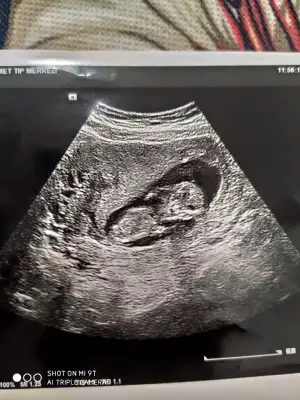

Erkek görünüyor emin olamadimMerhaba benimki de 12 haftalık sizce cinsiyet nedir kendini sakladı ilk bebeğim sağlıklı hayırlı olsun da insan merak ediyor işte![]()

Canım bende atsan bana da tahminde bulunur musunErkek gibi sanki net değil.usg varda başka paylaşın

En iyi 11 12 13 haftalar olmalı şimdilik sanki erkek yinede istediğim haftalar olursa paylasin10.hafta acaba belli olan bişi var mı☺

En iyi 11 12 13 haftalar olmalı şimdilik sanki erkek yinede istediğim haftalar olursa paylasin